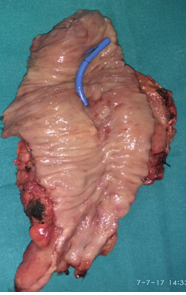

Specimen ( pancreatic head ) following modified Whipple’s operation (Courtesy Dr. V. Penopoulos)